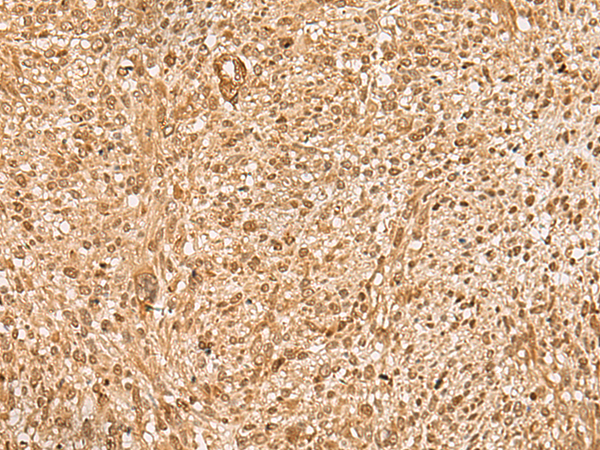

分类: 科研抗体货号: P09946别名: EXT; LGS; TTV; LGCR; TRPS2应用: IHC反应种属: Human, Mouse